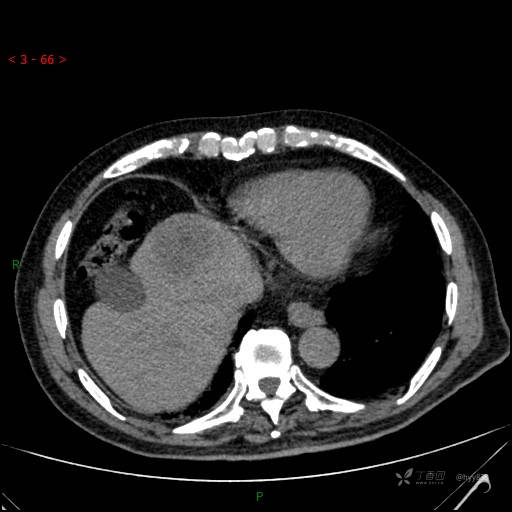

年龄:71岁

性别:男

简要病史: 间断发热、咳嗽3天,超声发现肝占位

临床诊断:肝占位

延迟期

肝脓肿 (73)